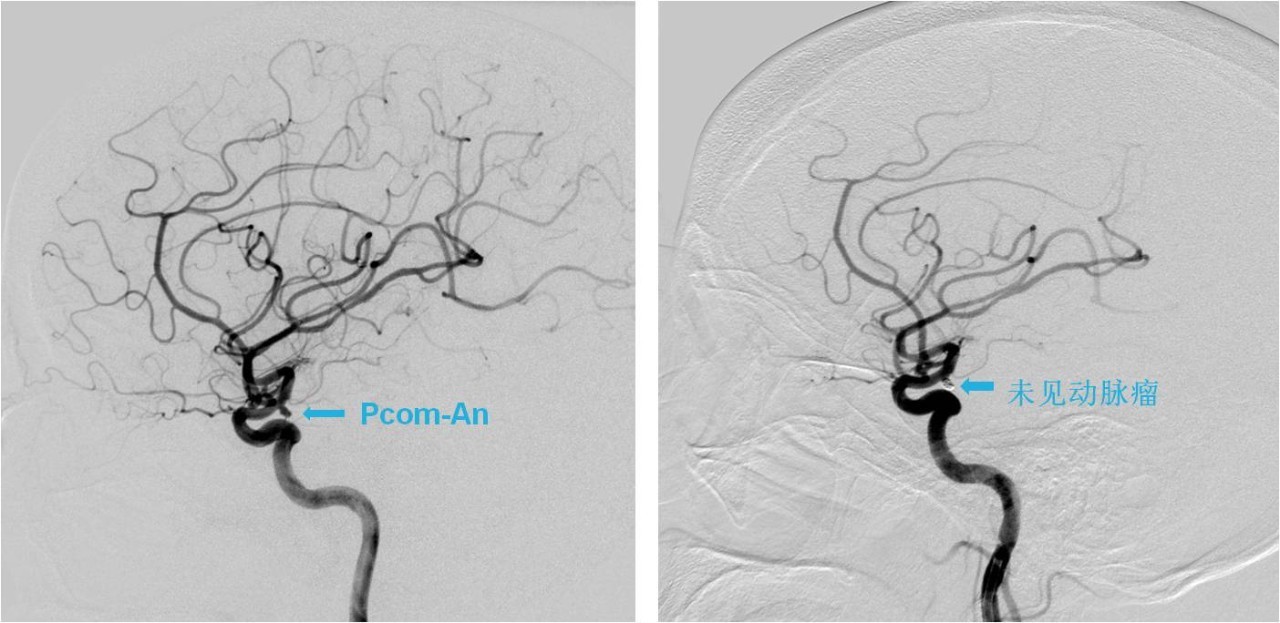

病例3:后交通动脉未破裂动脉瘤栓塞

》女性,23岁,因间断头痛、头晕6个月,加重2天入院,头痛全脑胀痛,不伴有恶心、呕吐,无耳鸣及听力减退,行头颅CT后按“头痛待查”收入我科。

》入院时查体:神经系统查体未见阳性定位体征。

术前、术后DSA对比

》DSA检查发现右侧后交通动脉动脉瘤,全麻下行颅内动脉瘤栓塞术。